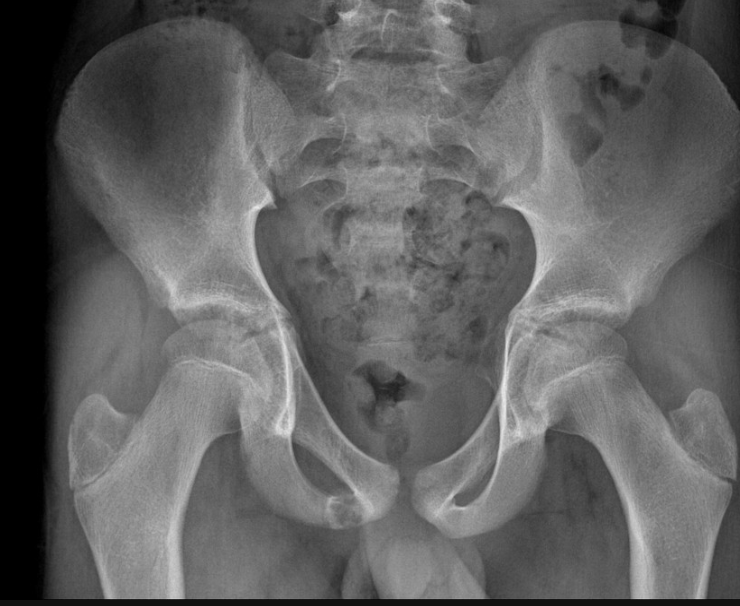

Masculino, 12 anos

Síndrome da sincondrose isquiopúbica assimétrica (Doença de Van Neck-Odelberg)

Variante da normalidade (em geral assintomático)

Crianças

Alargamento e radioluscência na sincondrose isquiopúbica, que simula neoplasias, infecção;